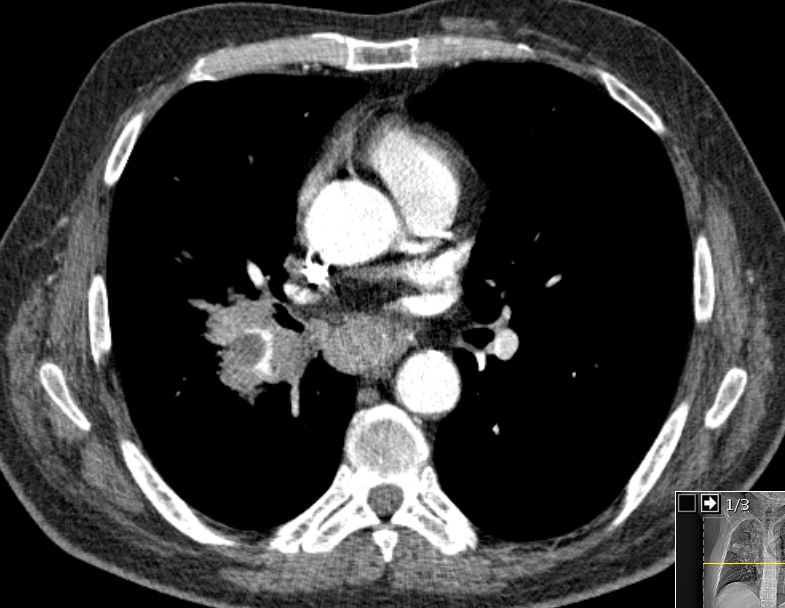

| Lymphknoten Karina | Die Karina wird durch eine große LK - Metastase

aufgespreizt.![]() |